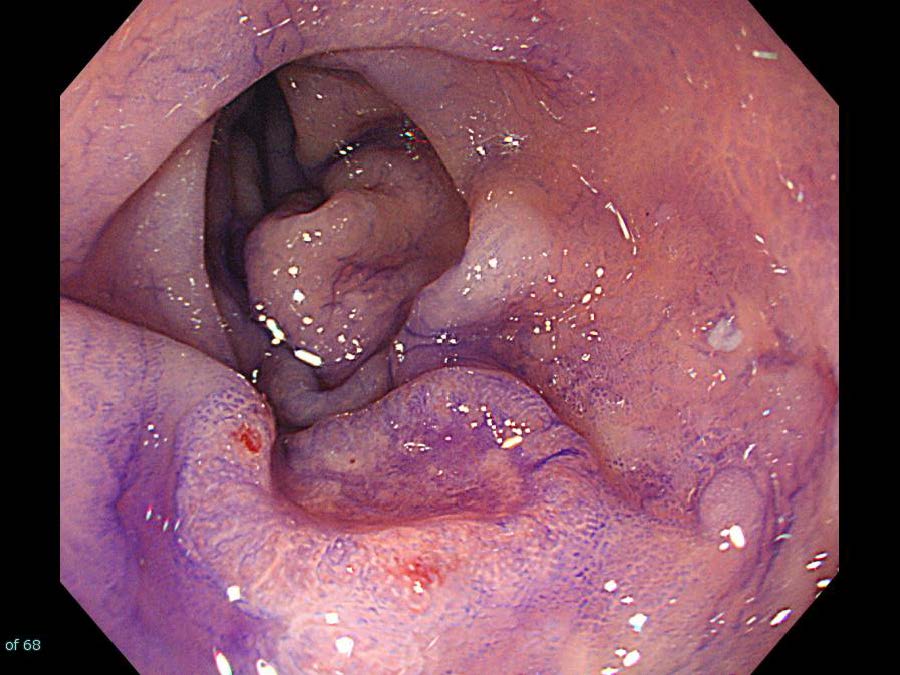

消化管Mapping~大腸~ 2021.10.27

消化管Mapping~大腸~

消化管Mapping